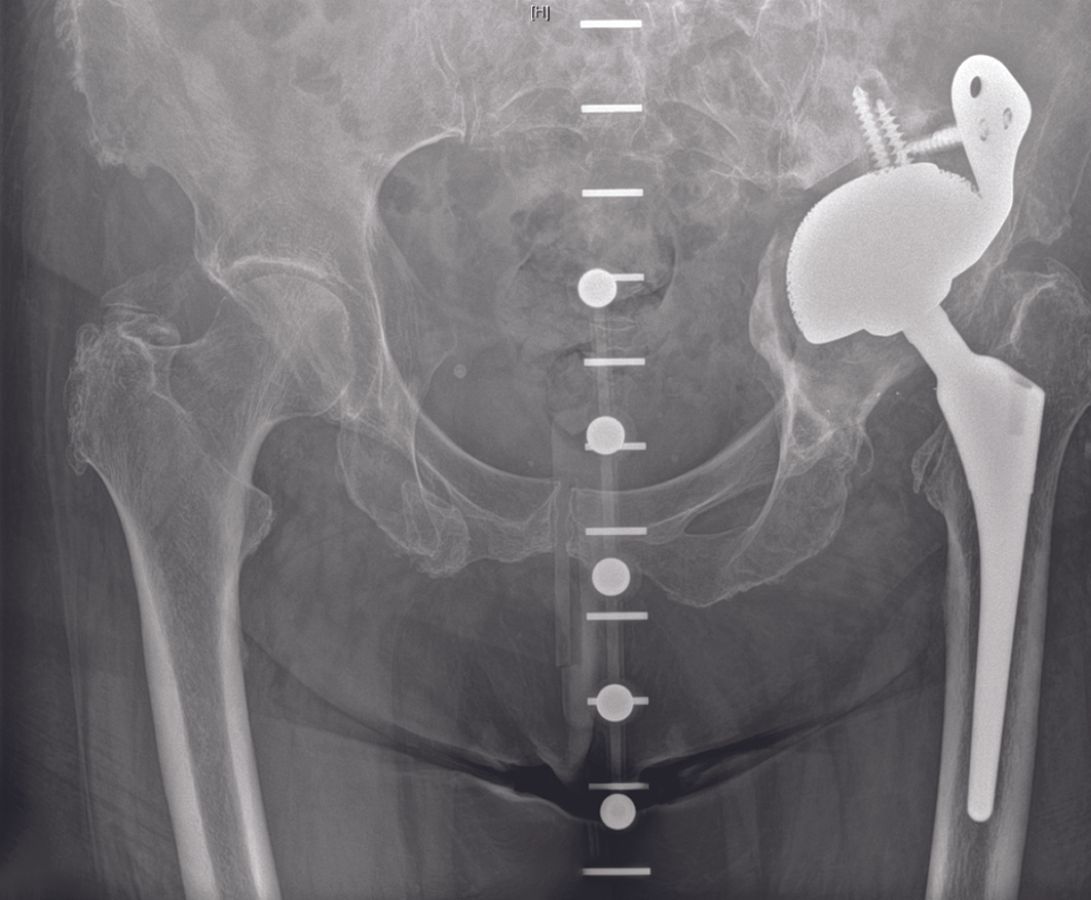

The clinical articles address two major domains. In revision acetabular surgery, contributions examine cup-cage reconstruction for severe acetabular bone loss and pelvic discontinuity alongside patient-matched 3D-printed implants for Paprosky 3 acetabular defects guided by bone quality assessment. In primary knee arthroplasty, the issue explores an extension gap first technique applying adjusted mechanical alignment to minimize soft tissue releases, complemented by a systematic approach to total knee arthroplasty in posttraumatic osteoarthritis.